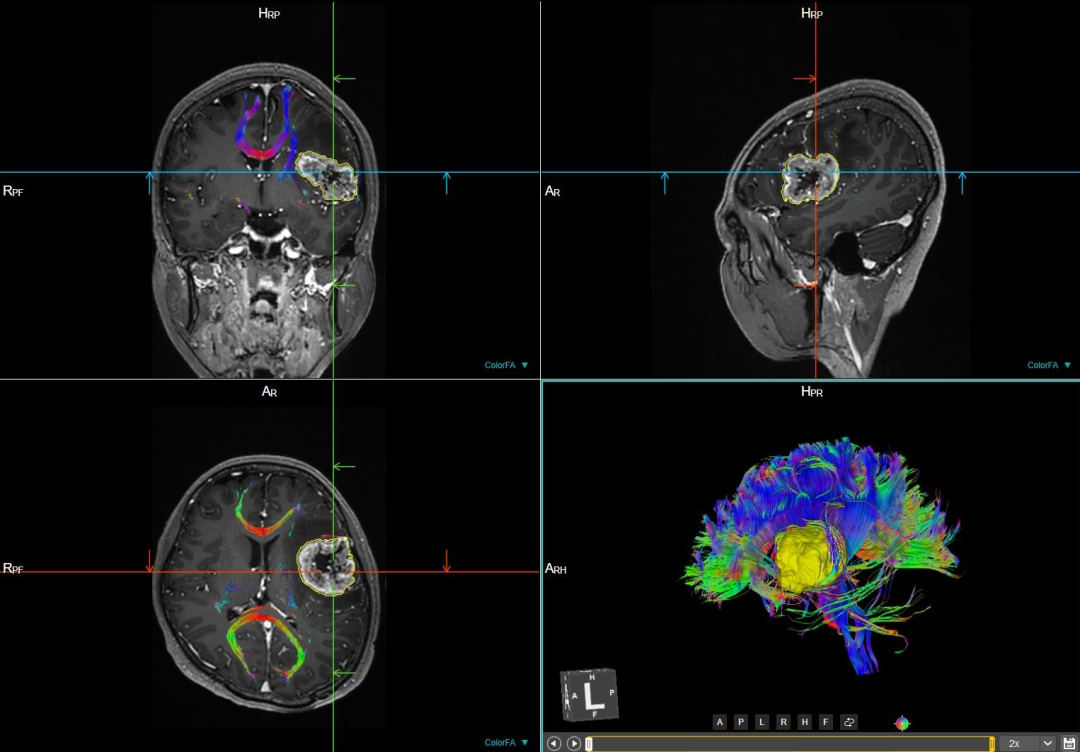

DTI 和 BOLD

弥散张量成像(DTI)和血氧水平依赖功能成像(BOLD)联合应用可以显示神经纤维传导束,并能较准确地反映脑功能区,对颅内肿瘤的术前评估和术后随访具有指导意义。

联影磁共振怎么样更先进、更高效、更精准—联影3.0T超导磁共振落户武城县人民医院_https://www.jmylbn.com_新闻资讯_第17张